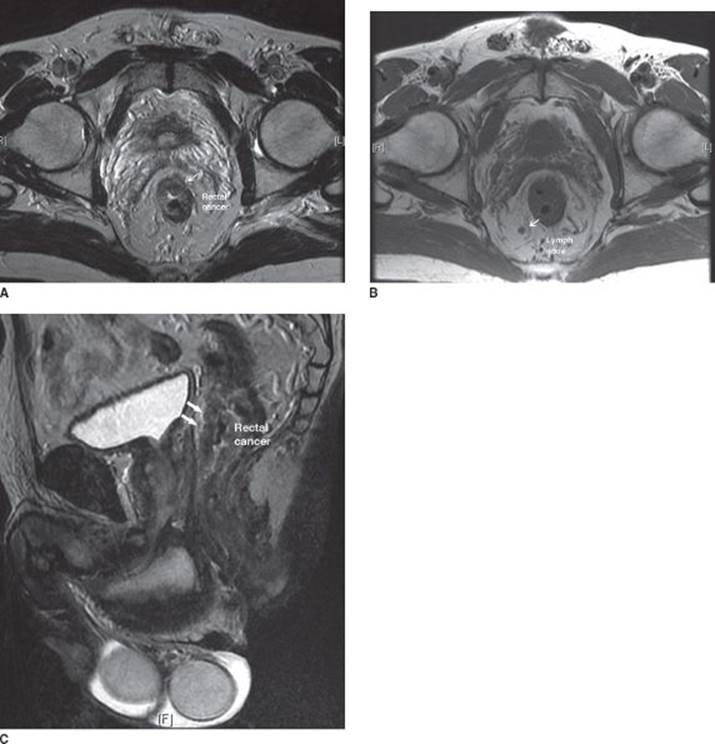

The degree of tumor fixity in the pelvis is related to the depth of penetration of the primary lesion through the rectal wall. Mobile lesions are often limited to the mucosa, submucosa (cT1), or muscularis propria (cT2), whereas tethered lesions generally represent tumors extending into the perirectal fat or the mesorectum (cT3). Fixed tumors can extend into surrounding anatomic structures such as the prostate, seminal vesicles, or vagina (cT4). Many rectal cancer patients present without pain. However, when pain is present it indicates probable involvement of the sphincter by tumor. Tumors that are painful often extend into the external sphincter complex. ERUS (Figure 1) and phased array magnetic resonance imaging (MRI) (Figure 2) are currently the best imaging modalities for staging of rectal cancer, capable of accurately staging the primary lesion with up to 90% accuracy and locoregional lymph nodes with an accuracy of as much as 80%. ERUS is slightly better than MRI in the staging of early lesions, while MRI is preferable for staging very bulky lesions with questionable invasion into surrounding organs (T4 lesions).

FIGURE 2 • MRI demonstrating the primary rectal cancer (A) and the mesorectal adenopathy (B) on axial imaging. (C) demonstrates the tumor in the sagittal plane.